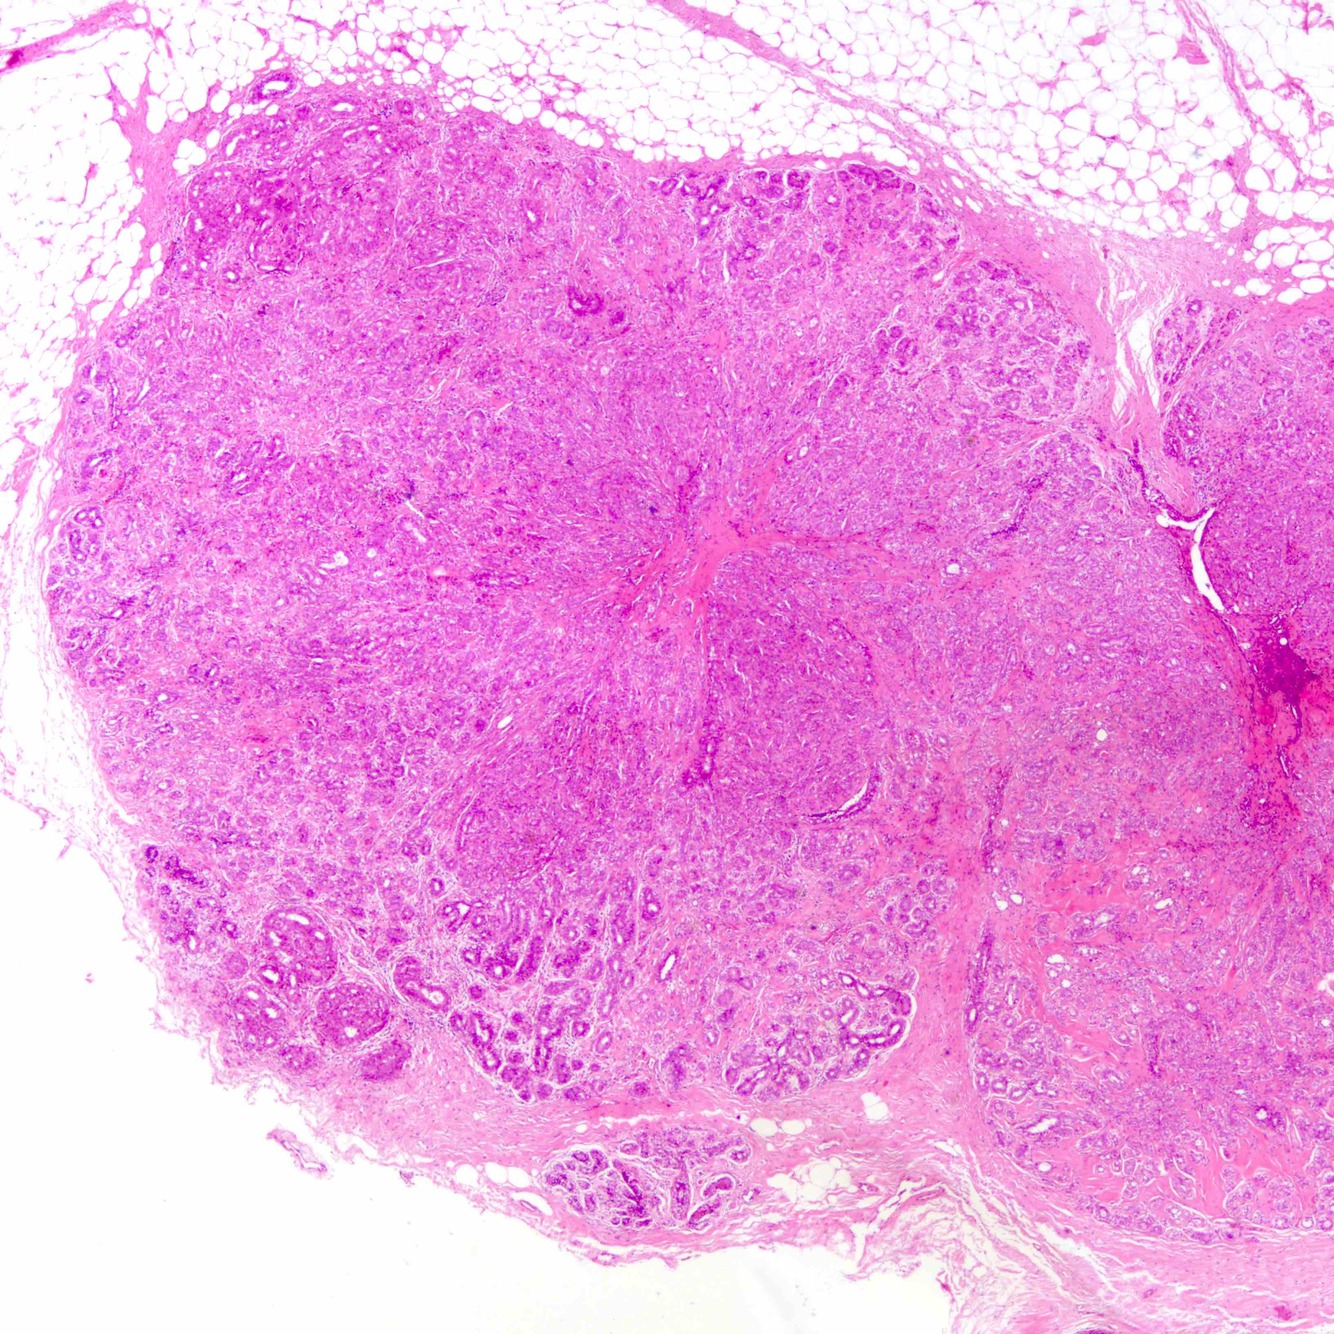

Phyllodes tumor

Biphasic tumor composed of spindled stromal cells and benign epithelial cells. Stromal cellularity is variable, and ranges from paucicellular to hypercellular. Prominent and exaggerated intracanalicular pattern with “leaf-like” projections into variably dilated lumina.

Shown is a benign phyllodes tumor, with a paucicellular stroma and stromal condensation under the epithelial-lining of the spaces.

Increased incidence in Li Fraumeni syndrome. Presents as a palpable, painless breast mass. Can have heterologous elements that are malignant.

Molecular: MED12 and RARA mutations in benign phyllodes tumors.

TERT promoter, ERBB4, TP53, EGFR, PIK3CA, and RB1 in borderline or malignant phyllodes tumors.